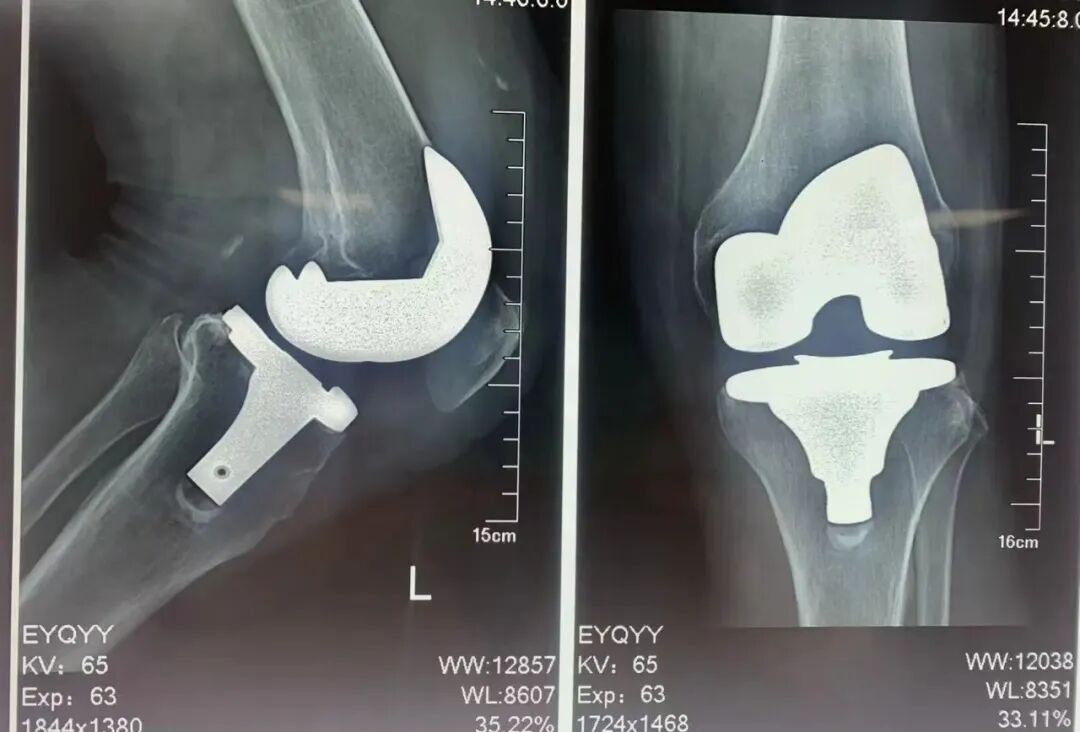

术后影像显示,人工膝关节位置良好,关节力线得到纠正。多年来,恩阳区人民医院骨科团队已经成功完成了近200例人工膝关节、髋关节置换手术。在与重庆医科大学附属第一医院建立紧密型医联体后,重医附一院将骨科团队将对恩阳区人民医院骨科团队提供强有力的技术支撑,协助我院提升骨科技术水平,为恩阳辖区骨科患者提供更优质的医疗服务。